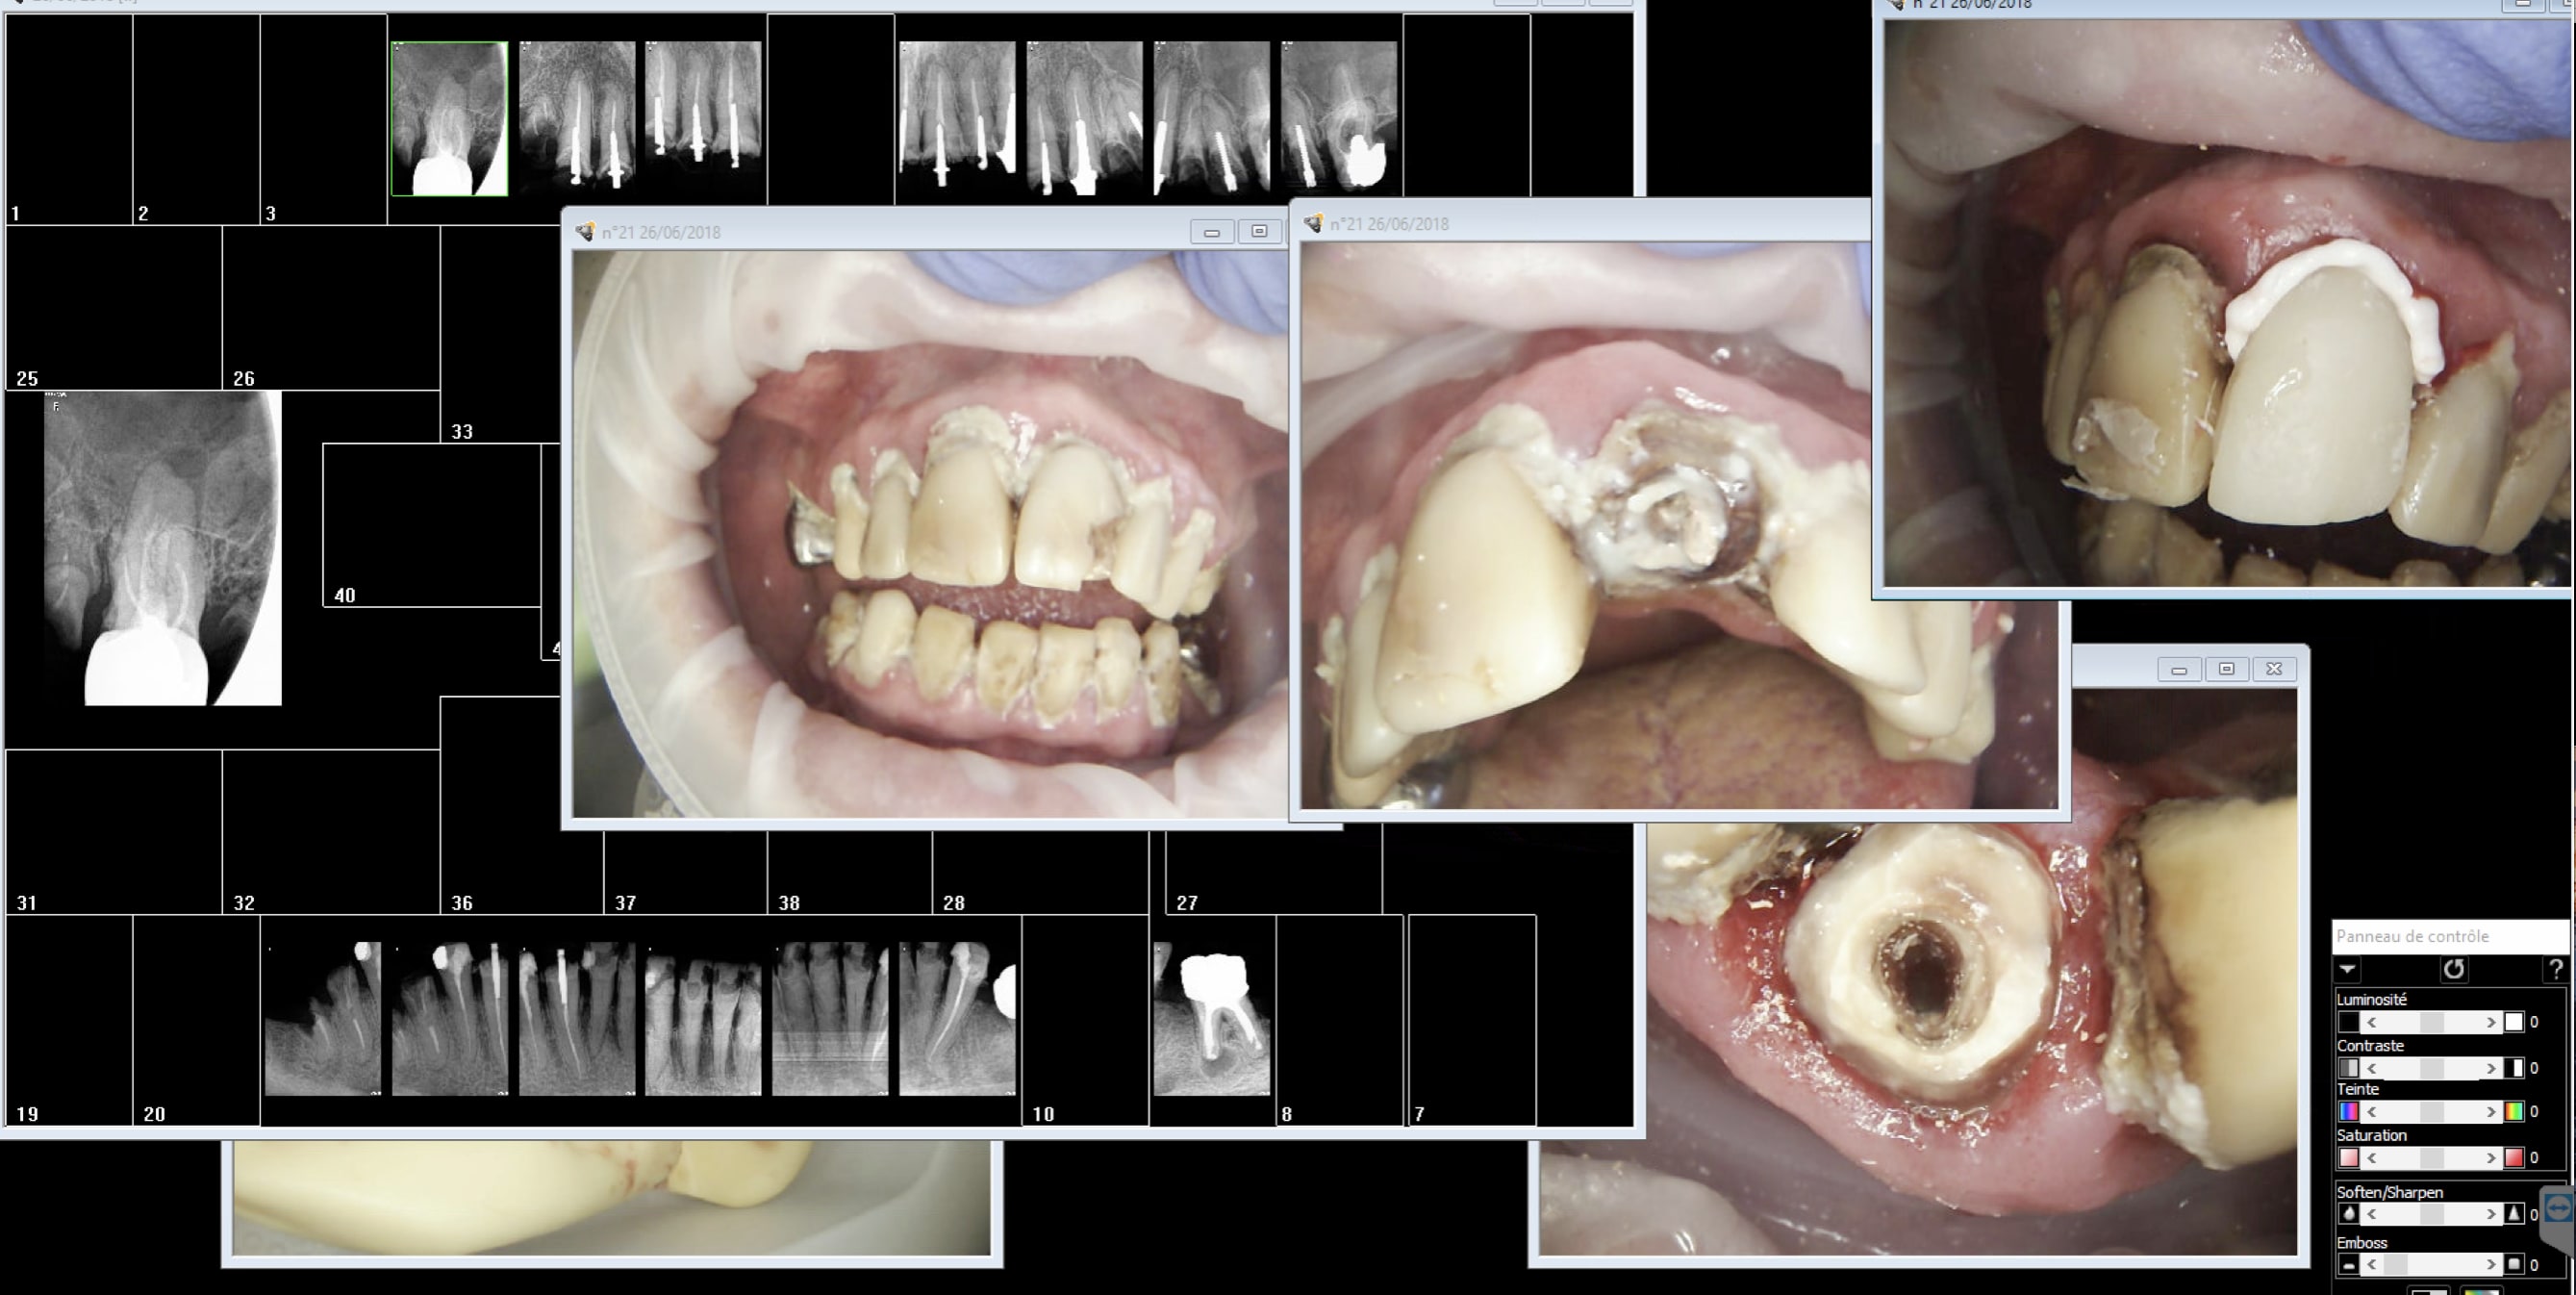

Une fois que tu auras fais tes devoirs petit, peut etre auras tu le temps de soigner ton patient. "de connaître l’état de la sphère oro-faciale du patient " Quelques clichés radio et photos ca suffit non ? Ou faut écrire un roman ? Status complet. Indication : antécédents de soins intensifs. Interprétation : c'est la merde, Orientation diagnostique :A ton avis ? -)))